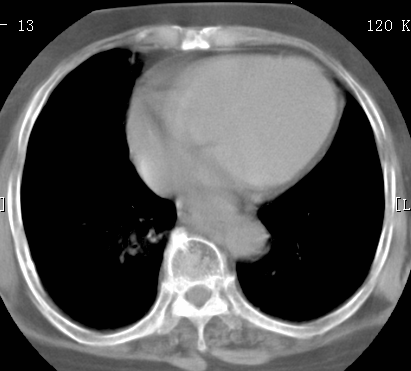

标题: CT26680:肺部右下肺静脉干结节的界定 [打印本页]

标题: CT26680:肺部右下肺静脉干结节的界定

经追查说有支扩咯血病史,但不确定

考虑1、周围型肺癌,2肺静脉畸形,前者可能大,建议增强检查。

考虑1、周围型肺癌,2肺静脉畸形,前者可能大,建议增强检查。支持!

不排除右肺下叶周围型肺癌可能。

中心型肺癌,纤支镜可帮助明确。